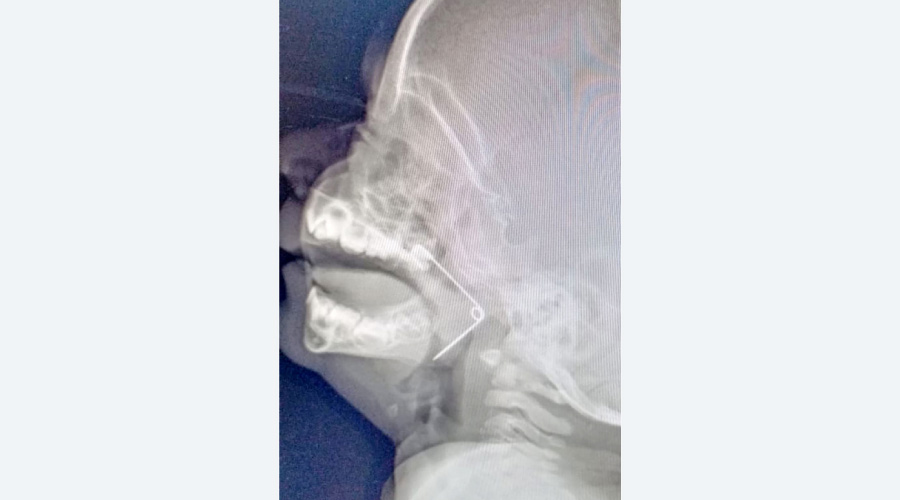

text_fieldsകുഞ്ഞിെൻറ തൊണ്ടയിൽ സേഫ്റ്റിപിൻ കുടുങ്ങിയതിെൻറ എക്സ്റേ ദൃശ്യം

കൊല്ലം: കളിക്കുന്നതിനിടെ പത്തുമാസം പ്രായമുള്ള കുഞ്ഞിെൻറ തൊണ്ടയിൽ കുടുങ്ങിയ സേഫ്റ്റിപിൻ പുറത്തെടുത്തു. കരുനാഗപ്പള്ളി കെ.എസ് പുരം സ്വദേശി ശിഹാബുദ്ദീൻ- സുലേഖയുടെ ദമ്പതിമാരുടെ മകൻ മുഹമ്മദ് ഇസിനാണ് സേഫ്റ്റിപിൻ വിഴുങ്ങിയത്. തുറന്നിരുന്ന പിൻ ആയതിനാൽ വായ അടക്കാൻ കഴിയാതെവന്നു.

സേഫ്റ്റി പിന്നിെൻറ മുകൾ ഭാഗം മൂക്കിെൻറ പിന്നിലേക്കും കൂർത്ത ഭാഗം ശ്വാസനാളത്തിെൻറ മുകളിലും തറച്ചിരുന്നതാണ് കൂടുതൽ പ്രശ്നം സൃഷ്ടിച്ചത്. ഇ.എൻ.ടിക്ക് പുറമെ ക്രിട്ടിക്കൽ കെയർ അനസ്തേഷ്യ വിഭാഗങ്ങളിലെ വിദഗ്ധരുടെ ഏകോപിത പ്രവർത്തനമാണ് ശസ്ത്രക്രിയ വിജയകരമാക്കിയതെന്ന് ആശുപത്രി അധികൃതർ അറിയിച്ചു.